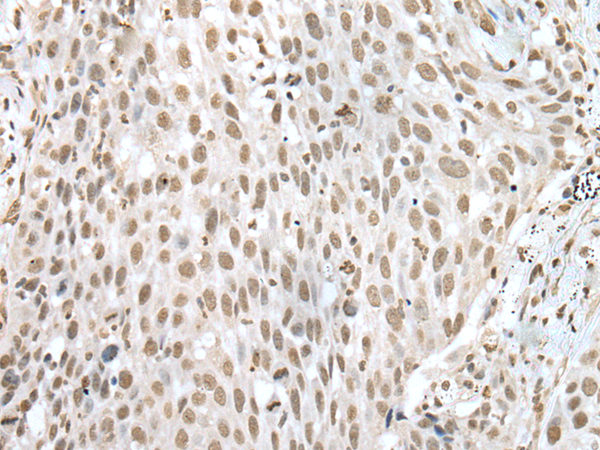

ELISA, IHC

IHC positive control:

Human lung cancer and human gastric cancer

IHC Recommend dilution: